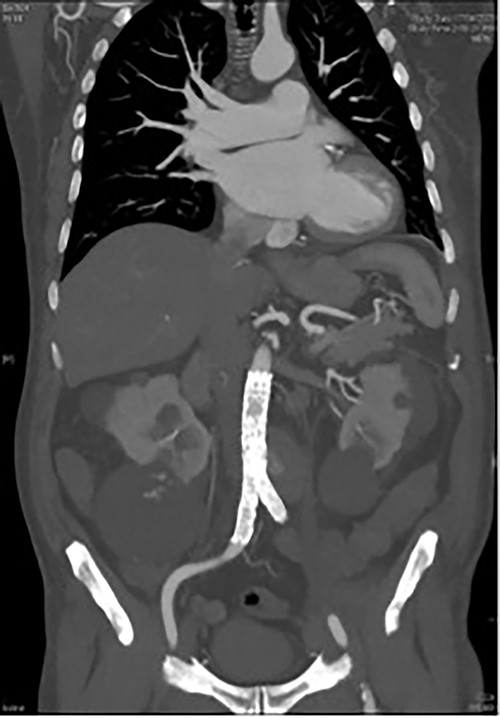

A 73-year-old male presented with a 1-week history of back pain on a background of hypertension, atrial fibrillation and bladder cancer. Computed tomography (CT) angiography demonstrated a 47 × 46 × 47 mm saccular aortic pseudoaneurysm of the infrarenal aorta with a contained rupture (Fig. 1). The patient remained hemodynamically stable with mildly elevated inflammatory markers (C-Reactive Protein (CRP), 85 mg/l, white cell count (WCC) 6.5 × 109/l). The abdominal aorta 5 months previously was normal on CT when a course of intra-vesical BCG for transitional cell carcinoma of the bladder had been ceased due to the development of fevers and syncope. Thus, Mycobacterium bovis involvement of the false aneurysm was suspected. Emergent endovascular repair was performed with a covered stent graft system successfully excluding the ruptured aneurysm sac on post-operative CT angiogram. A CT-guided fine needle aspirate of the aneurysmal sac was later conducted (Fig. 2). PCR of the aspirate returned a low-positive result confirming the diagnosis with M. bovis subsequently isolated on culture. Empirical antibiotics were ceased and he was commenced on a planned 18-month antituberculosis regimen of ethambutol, isoniazid and rifampicin guided by gene deletion analysis (GeneXpert MTB/RIF Ultra assay). Fluorodeoxyglucose-positron emission tomography (FDG-PET) scan was used to monitor the level of activity of the infection (Fig. 3). The patient was discharged home on Day 10 of admission. Aneurysm sac size was decreased at 3 and 6 months on CT angiogram and FDG-PET but there was ongoing FDG avidity around the aneurysm sac; there were no other sites of involvement. The patient remains otherwise well and has returned to his premorbid activities.

CT angiography post endovascular repair demonstrates an aorto-bi-iliac stent graft extending from the infrarenal aorta to the common iliac arteries with a small area of persistent filling of the pseudoaneurysm that subsequently resolved.